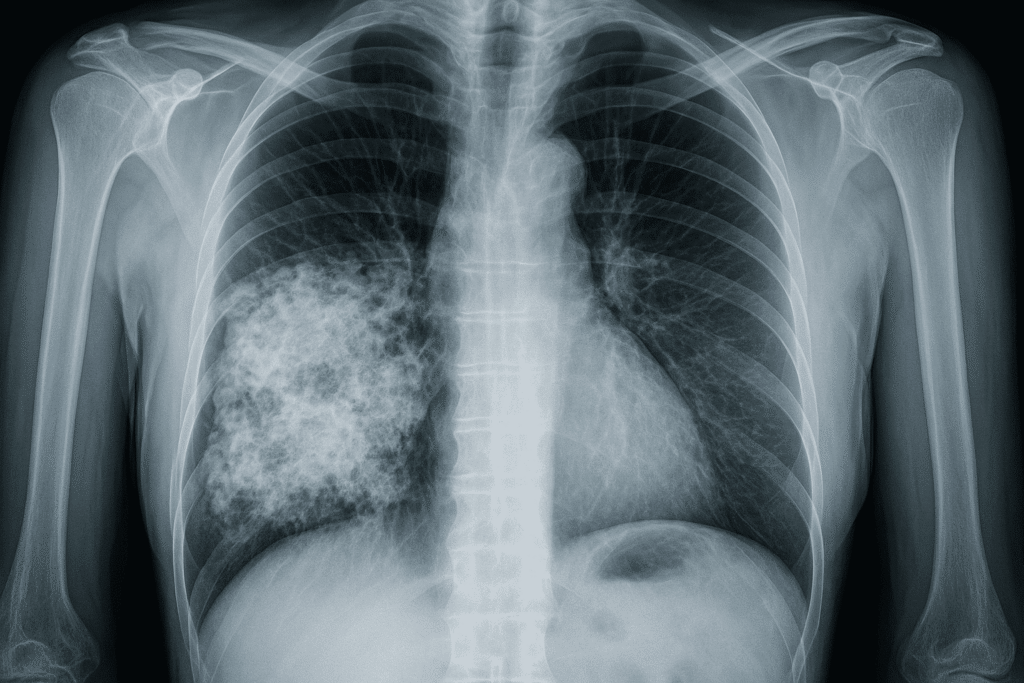

1. Chest X-ray

• A basic image of the lungs

• Can show tumors, fluid, or other lung changes

2. CT (Computed Tomography) Scan

• A more detailed 3D image of the lungs

• Can find small tumors that might not show up on a regular X-ray

• Asbestos Lung Cancer: Detected with imaging (like X-rays or CT scans), followed by biopsy.